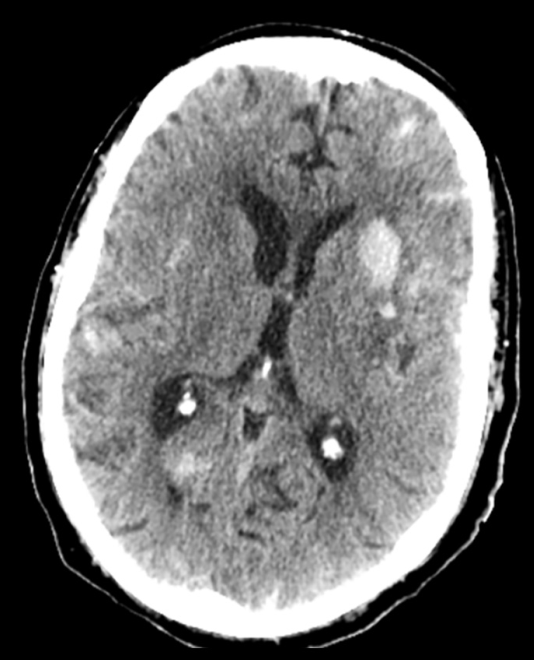

然而,在疗养机构,主管医生自行决定重新启动了阿哌沙班5mg每日两次的治疗。出院八周后,在一次血液透析后,患者出现精神状态改变、四肢瘫痪和吞咽困难。头部CT显示多灶性颅内出血:左额叶最大血肿(2.3×1.5 cm),累及双侧岛叶下区和左基底节区,伴蛛网膜下腔出血,有轻度占位效应但无中线移位。这些表现与凝血功能障碍相符。

Axial computed tomography (CT) images of the head. CT scan of the head revealed multifocal intracranial hemorrhage with numerous acute hemorrhages across multiple compartments. The largest intraparenchymal hemorrhage, measuring 2.3×1.5 cm, was in the left frontal lobe, also involving the bilateral subinsular region and left basal ganglia. A mild mass effect was present without midline shift, along with subarachnoid hemorrhage.